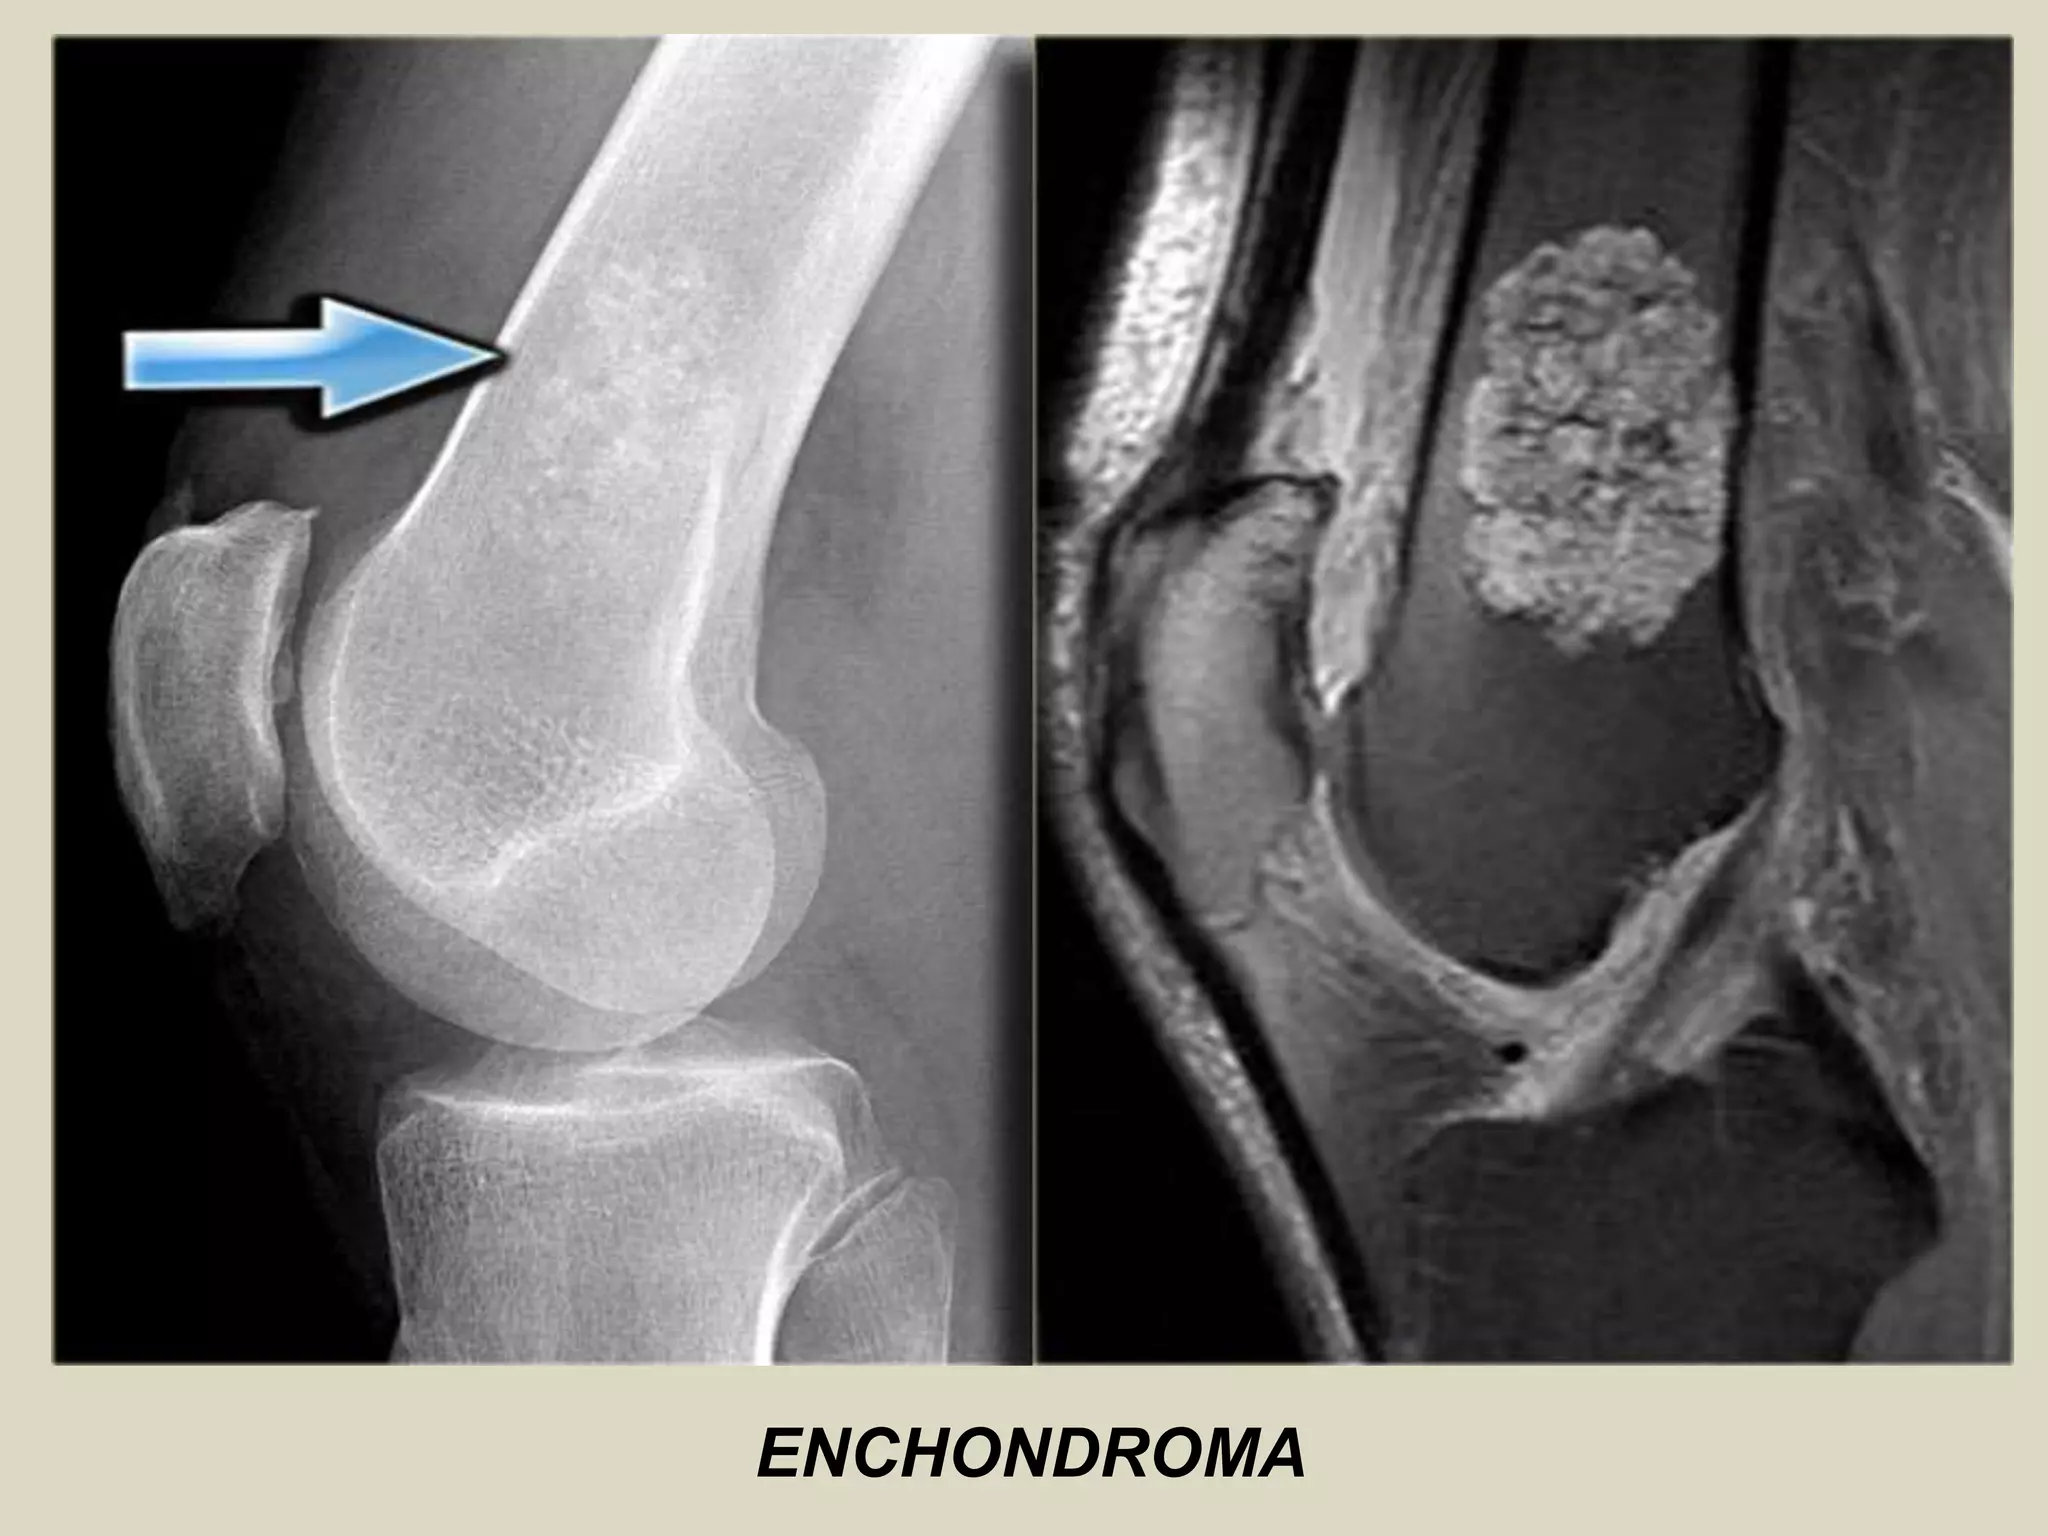

Definition: Benign hyaline cartilage neoplasm of medullary bone.

- Relatively common, accounting for 10-25% of all benign bone tumors.

Sites of involvement: Usually metaphyseal-diaphyseal in location and frequently affect the short tubular bones of the hands.

Imaging:

- Well marginated tumors that vary from radiolucent to heavily mineralized.

- Mineralization pattern is characteristic, consisting of punctate, flocculent, or ring and arc pattern.

- Long bone tumors are usually centrally located within metaphysis.

- More extensive endosteal erosion is considered suspicious for low grade chondrosarcoma.

- Cortical destruction and soft tissue invasion should never be seen in enchondromas and would be most

consistent with chondrosarcoma.

ENCHONDROMA.